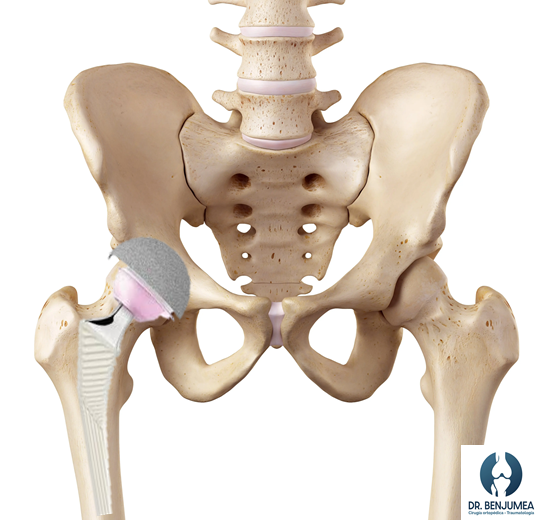

¿Cómo es una prótesis de cadera?

La prótesis tiene dos componentes fundamentales, que sustituirán la cabeza femoral y al acetábulo. El sustituto femoral se llama vástago protésico y se coloca en el canal del fémur. Para poder moverse de manera adecuada, el vástago termina en una cabeza redonda, que se mueve sobre una copa, el acetábulo protésico. Para que ambas piezas durante el movimiento no choquen directamente, lo que provocaría un desgaste acelerado, colocamos una pieza llamada inserto, que puede ser de cerámica o de polietileno. Las prótesis suelen estar compuestas de aleaciones metálicas lo que le dan sus características principales de resistencia y durabilidad.